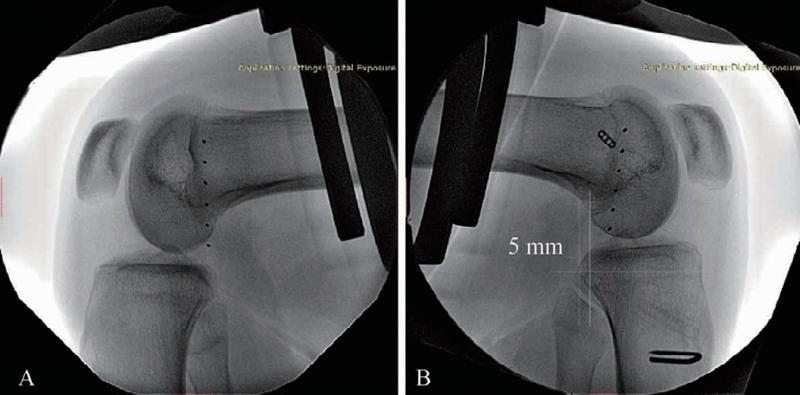

后方应力位或跪位X线检查是诊断PCL损伤的可靠方法(图6),对比健侧,后移增加0~7mm为PCL部分损伤(图7),8~11mm为单纯PCL全部断裂(图8),12mm以上可能为PCL和PLC等其他结构合并损伤(图9)。

图7 PCL部分损伤X线影像

应力位X线片(B)示胫骨后移超过健侧(A)5mm